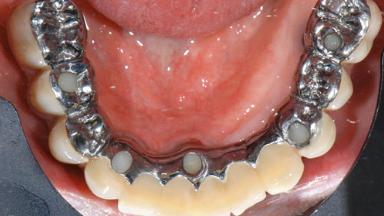

Repeated Acrylic Fractures on a Mandibular Fixed Full-arch Implant-supported Metal/Acrylic Prosthesis

A 77-year-old male patient was referred for the management of frequent and repeated acrylic fracture of his existing mandibular fixed full-arch implant-supported metal/acrylic prosthesis. He also complained about softtissue soreness and the lack of retention and stability of his maxillary removable partial metal/acrylic prosthesis. Both prostheses had been delivered two years previously as part of his full-mouth rehabilitation (caries, tooth wear, tooth fracture). His medical history revealed high blood pressure, controlled with the use of antihypertensive medication.

SAC Level Complex

Defining Characteristics Fully edentulous lower jaw to be rehabilitated with an implant-borne fixed dental prosthesis

Retention Screw-retained, with 4 or more splinted implants Screw-retained, with 4 or more splinted implants

Inter-Arch Distance Excessive (mechanical leverage issues) or restricted (space for components)

Bruxism Present